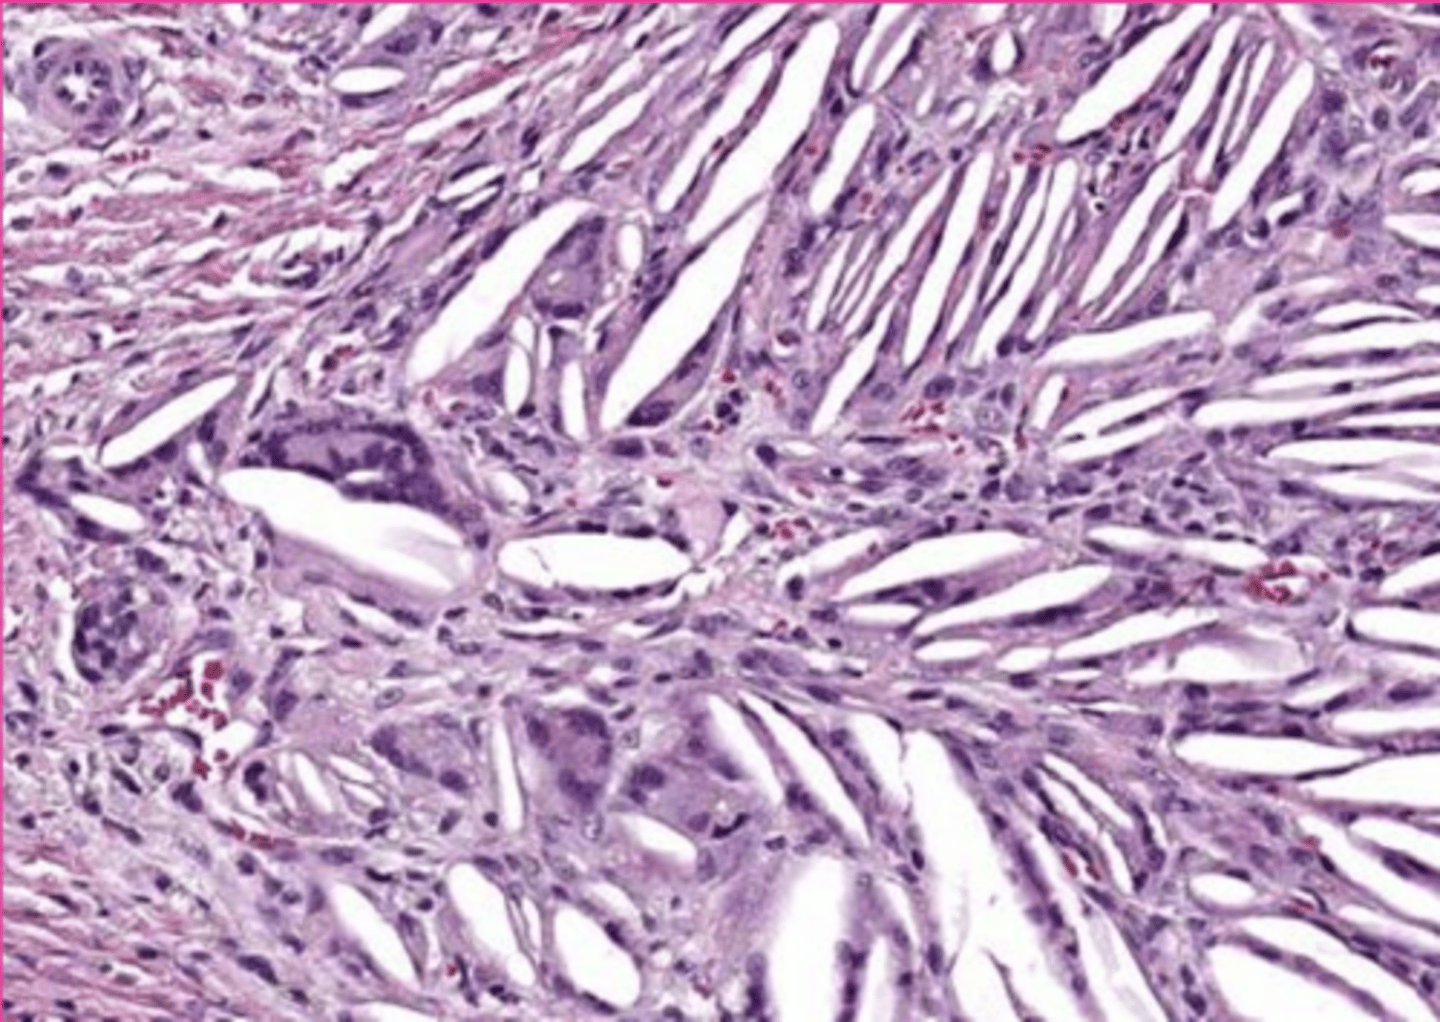

renal gout tophi

Describe this extracellular accumulation in the kidney